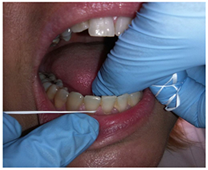

Kit de higiene dental

Explicación de limpieza lingual

Explicación de técnica de cepillado

Explicación del uso de hilo dental